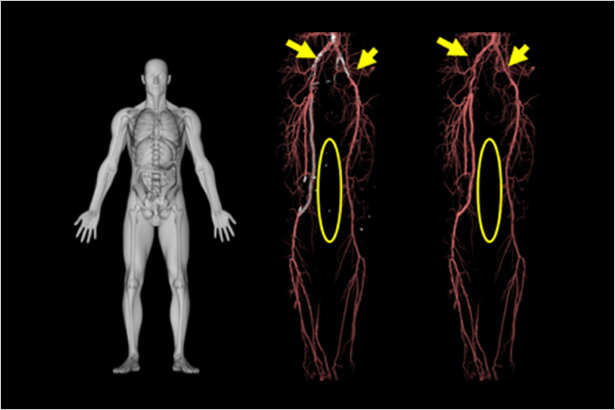

在柔性體部血管成像中,可一站式獲得去骨,去鈣化,斑塊,支架的血管圖像。